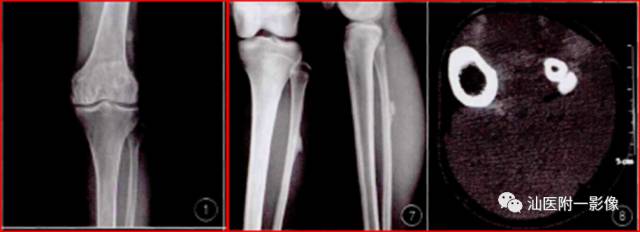

5.奇异性骨旁骨软骨瘤样增生 (新增)

•奇异性骨旁骨软骨瘤样增生(BPOP),又称Nora病(NL),是一种较为少见的良性骨膜外增生性病变。

•最常发生于40岁左右,无性别差异。50%复发。

•主要位于手、足短骨旁(中/近节指/趾骨、掌骨、跖骨居多)。